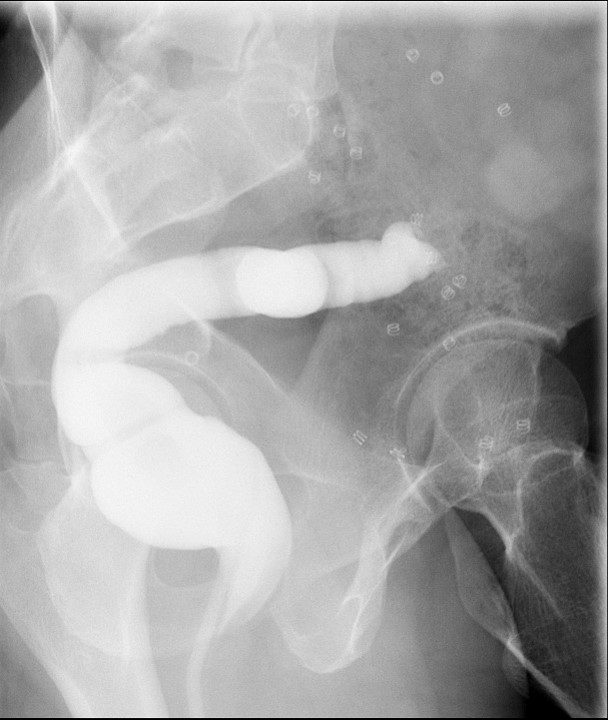

- Once you have the tube in the desired location, inject water soluble contrast material through the tube to verify location. Immediately after injection, obtain a spot image or do a screen capture showing final tube position.

- nasoduodenal

(key image 1)

- nasojejunal

(key image 2)

- Inject contrast material and obtain either a spot film or last image hold demonstrating the tube in the correct position.

(key image 3)

(key image 4)